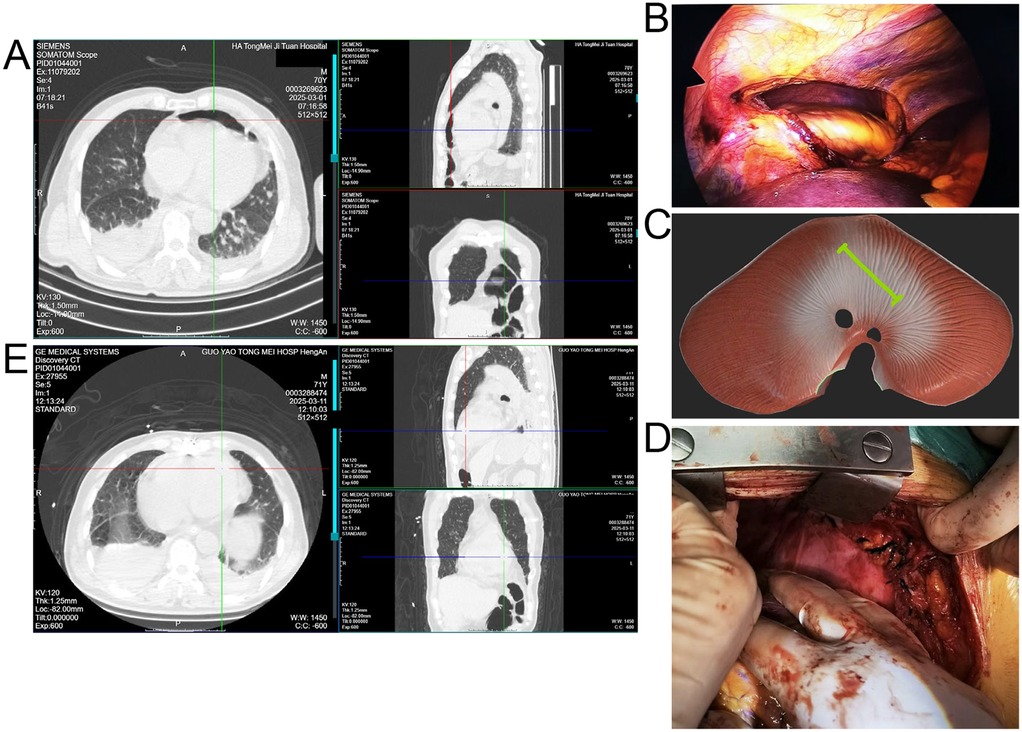

At an outside hospital, CT showed multiple right rib fractures and pulmonary contusion. Upon transfer to our center, repeat CT revealed bilateral lower lobe atelectasis, small pleural effusions, and a bowel gas shadow anterior to the heart, raising concern for diaphragmatic rupture with intrapericardial herniation (Figure 1A). Thoracoscopic exploration demonstrated no right-sided diaphragmatic or pericardial rupture, which had been suspected based on the outside CT. Laparoscopy was subsequently performed to allow a more comprehensive evaluation of the left hemidiaphragm, and it revealed a 10 cm tear with herniation of bowel and omentum into the pericardial sac (Figure 1B,C). The herniated contents were in direct contact with the epicardial surface of the heart. Because of the large size of the defect and the high tension on the incarcerated viscera, safe reduction and repair could not be achieved under minimally invasive conditions. Therefore, the procedure was converted to a median sternotomy, which provided optimal exposure for reduction of the herniated contents, suspension of the pericardium, and secure closure of the defect (Figure 1D).

Figure 1. (A) Preoperative CT showing right rib fractures, bilateral lower lobe atelectasis, pleural effusions, and bowel shadow anterior to the heart suggestive of diaphragmatic hernia. (B) Laparoscopic view of herniated bowel and omentum entering the pericardial sac through a left diaphragmatic defect. (C) Schematic illustration of the diaphragmatic tear (green line) and intrapericardial herniation. (D) Intraoperative image after reduction and pericardial repair via median sternotomy. (E) Postoperative CT confirming resolution of the hernia and lung re-expansion.

Postoperative CT confirmed resolution of the hernia and re-expansion of the lungs (Figure 1E). The patient was monitored in the ICU for 48 h and then transferred to the general ward. He experienced no major postoperative complications and was discharged on postoperative day 12 in good condition. At 3-month follow-up, he remained asymptomatic, and imaging confirmed sustained resolution of the hernia.